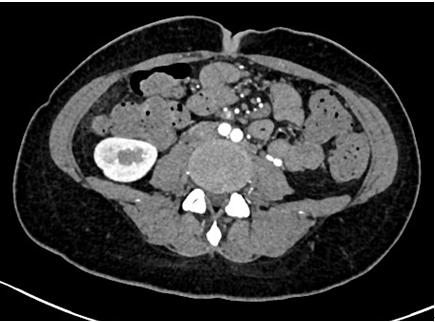

图2. 风湿免疫指标办好住院已经是1月13日下午四点了,介入科方淳主任及团队加班加点,当天晚上就为患者做了肠系膜动脉和静脉造影,结果没有发现大血管的问题,但是小血管充血、丰富,呈梳子样改变(称为“梳子征”,图1)。排除了肠系膜大血管的问题之后,高度怀疑肠系膜小血管炎可能,事不宜迟,赵家胜主任通过电话联系到风湿免疫科值夜班的王璇主治医生,王医生仔细询问了病史,了解到患者有过脱发和自发性流产的病史,结合本次肠道小血管炎的表现,高度怀疑系统性红斑狼疮引起的肠系膜血管炎。为了缓解患者的腹痛,挽救病人的生命,王璇医生基于对病情的判断,在化验结果尚未出来的情况下果断使用了糖皮质激素,第二天早上(1月14日)患者腹痛和恶心、呕吐即明显好转,患者胃口也开了,随后吃了点半流质,但下午又出现了腹痛和呕吐,这时化验结果也出来了(见图2),狼疮的标志性抗体-抗Sm抗体和ds-DNA抗体均阳性,证实了系统性红斑狼疮的诊断。赵主任和风湿免疫科汤建平主任共同查房后认为系统性红斑狼疮诊断明确,以急性腹痛起病,而且一发病就表现为狼疮危象的红斑狼疮少见,常规剂量激素疗效不佳,腹部CT结果显示肠壁水肿和胸腹水有进展(见图3、图4),需要立即进行大剂量激素冲击治疗。